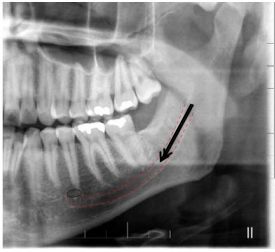

A radiografia panorâmica é a técnica extrabucal

mais solicitada em odontologia. Entre as suas

indicações estão a visão ampla do complexo

maxilomandibular, a avaliação da relação entre

dentes decíduos e permanentes, o

posicionamento de terceiros molares

inclusos/impactados, o estudo de anomalias

dentárias, a extensão de lesões patológicas e

alterações metabólicas, além do diagnóstico de

fraturas mandibulares e da ATM.

Fonte: Association between Facial Type and Mandibular Canal Morphology – Analysis in Digital Panoramic Radiograph..

Considerando a radiografia panorâmica apresentada, a estrutura anatômica indicada pela seta e pelo tracejado corresponde a:

Fonte: Association between Facial Type and Mandibular Canal Morphology – Analysis in Digital Panoramic Radiograph..

Considerando a radiografia panorâmica apresentada, a estrutura anatômica indicada pela seta e pelo tracejado corresponde a: